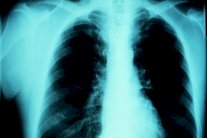

تلقى الأطباء والصيادلة العديد من المكالمات بخصوص صعوبات في التنفس ارتفع عدد المتوفين إثر ظاهرة ربو العواصف الرعدية إلى ستة أشخاص في مدينة ميلبورن الأسترالية. بالإضافة إلى ثلاثة آخرين في حالة حرجة. وتسببت الرياح والأمطار الشديدة يوم الإثنين في تأجيج آلاف الحالات من حساسية حبوب اللقاح في ولاية فكتوريا. وأُعلنت حالة التأهب القصوى في الخدمات الصيدلية والمستشفيات، إثر اتصال الآلاف للإبلاغ عن مشاكل في التنفس. وتظهر حالات ربو العواصف الرعدية في الربيع، إذ تصبح حبوب اللقاح رطبة، وتتكسر إلى أجزاء أصغر، وتدخل الرئة لتسبب مشاكل في التنفس. وتلقى أكثر من ثمانية آلاف شخص العلاج في المستشفيات. ويصاب بالربو شخص واحد من بين كل عشرة أشخاص في أستراليا، من بينهم حوالي 80 في المئة يعانون من الحساسية، خاصة المرتبطة بحبوب اللقاح. وتشهد مدينة ميلبورن فصل ربيع رطب، مما أدى إلى ظهور العديد من حالات الربو والحمى.